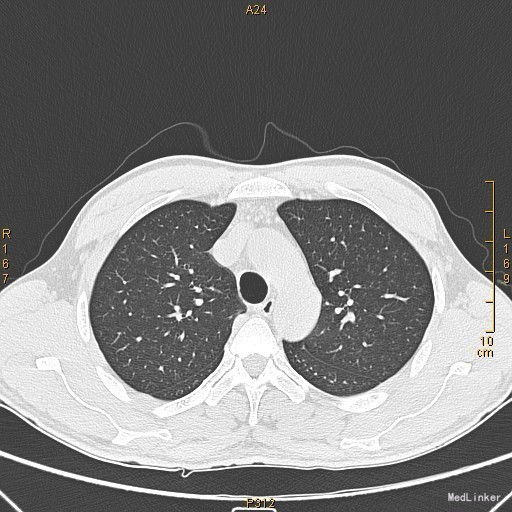

主诉:左眼睑下垂1年,加重半年。病史:患者1年前无明显诱因出现左眼睑下垂,抬起困难,伴视物重影,无言语不能、吞咽困难,无发热、头痛、恶心、呕吐、头晕、视物旋转、肢体麻木、饮水呛咳、视物模糊、肢体不自主运动、肢体抽搐、意识障碍、大小便失禁,休息后缓解,未予重视,半年来上述症状反复加重,10余天前至当地医院就诊,查新斯的明试验阳性,遂至我院神经内科就诊,胸部CT示:1、右肺尖钙化结节;2、胸腺增生。为了进一步治疗门诊拟“重症肌无力”收住我科。患者自起病以来,无发热、咳嗽、尿频、尿急、腹泻,无心悸、胸闷等,精神、食欲、睡眠好,体重无明显变化。

查体:左侧眼睑下垂,右侧眼裂宽10mm,左侧眼裂宽5mm。肺部查体未见异常。 辅查:新斯的明试验阳性。胸部CT示1、右肺尖钙化结节;2、胸腺增生。

该患者诊断“1.重症肌无力,眼肌型;2.右上肺钙化结节”明确,重症肌无力合并胸腺增生或胸腺瘤,有手术指征,我们为患者行胸腔镜下胸腺扩大切除术+右肺上叶楔形切除术。术后病理示:右上肺结节呈干酪样坏死,考虑结核。胸腺及纵隔脂肪均见淋巴增生。术后效果明显,患者左侧眼睑下垂较前好转,右侧眼裂宽10mm,左侧眼裂宽8mm,视物重影症状消失。